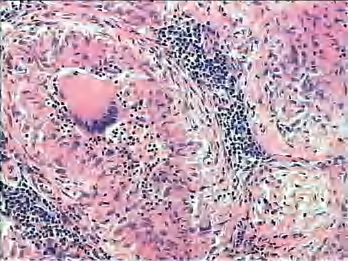

2.镜下 典型的肉芽肿中央为干酪样坏死,周边为上皮样细胞、郎罕巨细胞及炎细胞。以免疫反应为主时主要形成肉芽肿,称为增殖性结核;大部分伴有干酪样坏死,称为干酪性结核(图3-13、图3-14)。

图3-14 淋巴结结核,左上方可见一多核巨细胞